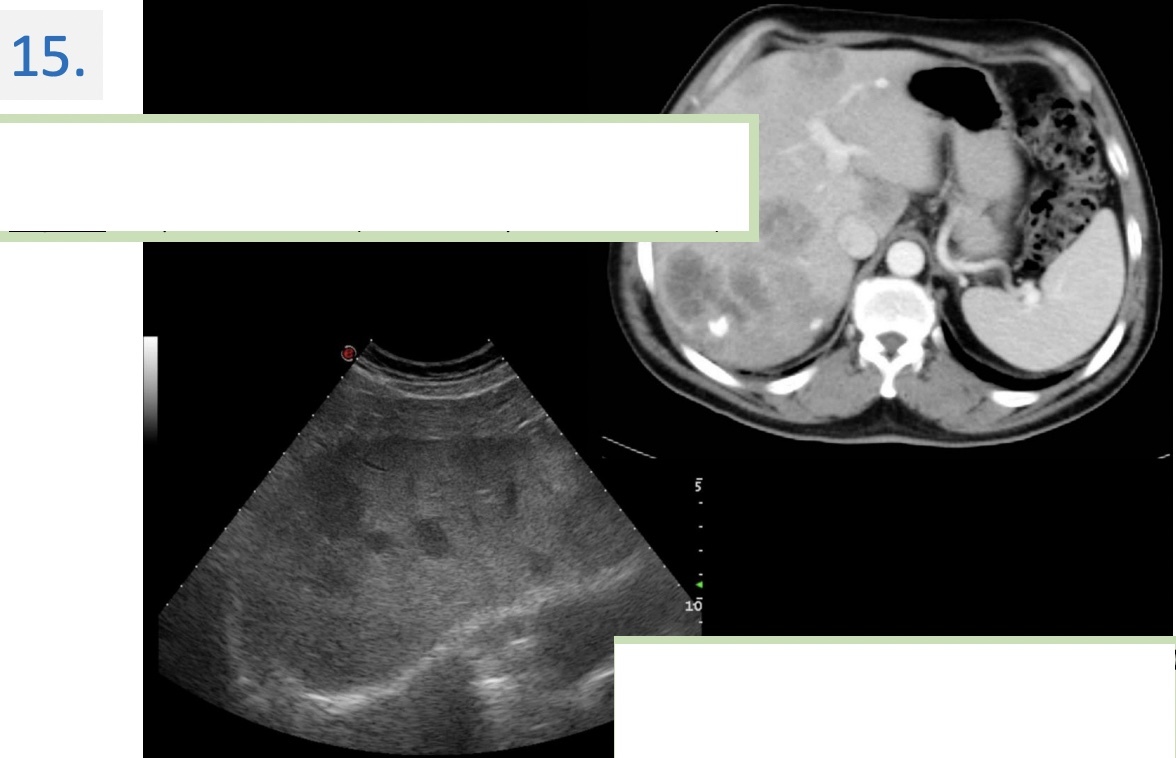

Modality:

Noncontrast CT

Region:

Upper abdomen, axial views

Radiologic sign:

-Diffusely & homogenously decreased density (cca. -20 HU) of the liver

(normal density is cca. 50-60 HU).

-The vessels (blue arrows) → denser -relative to the liver parenchyma-

Diagnosis:

Steatosis Hepatis (Fatty liver)